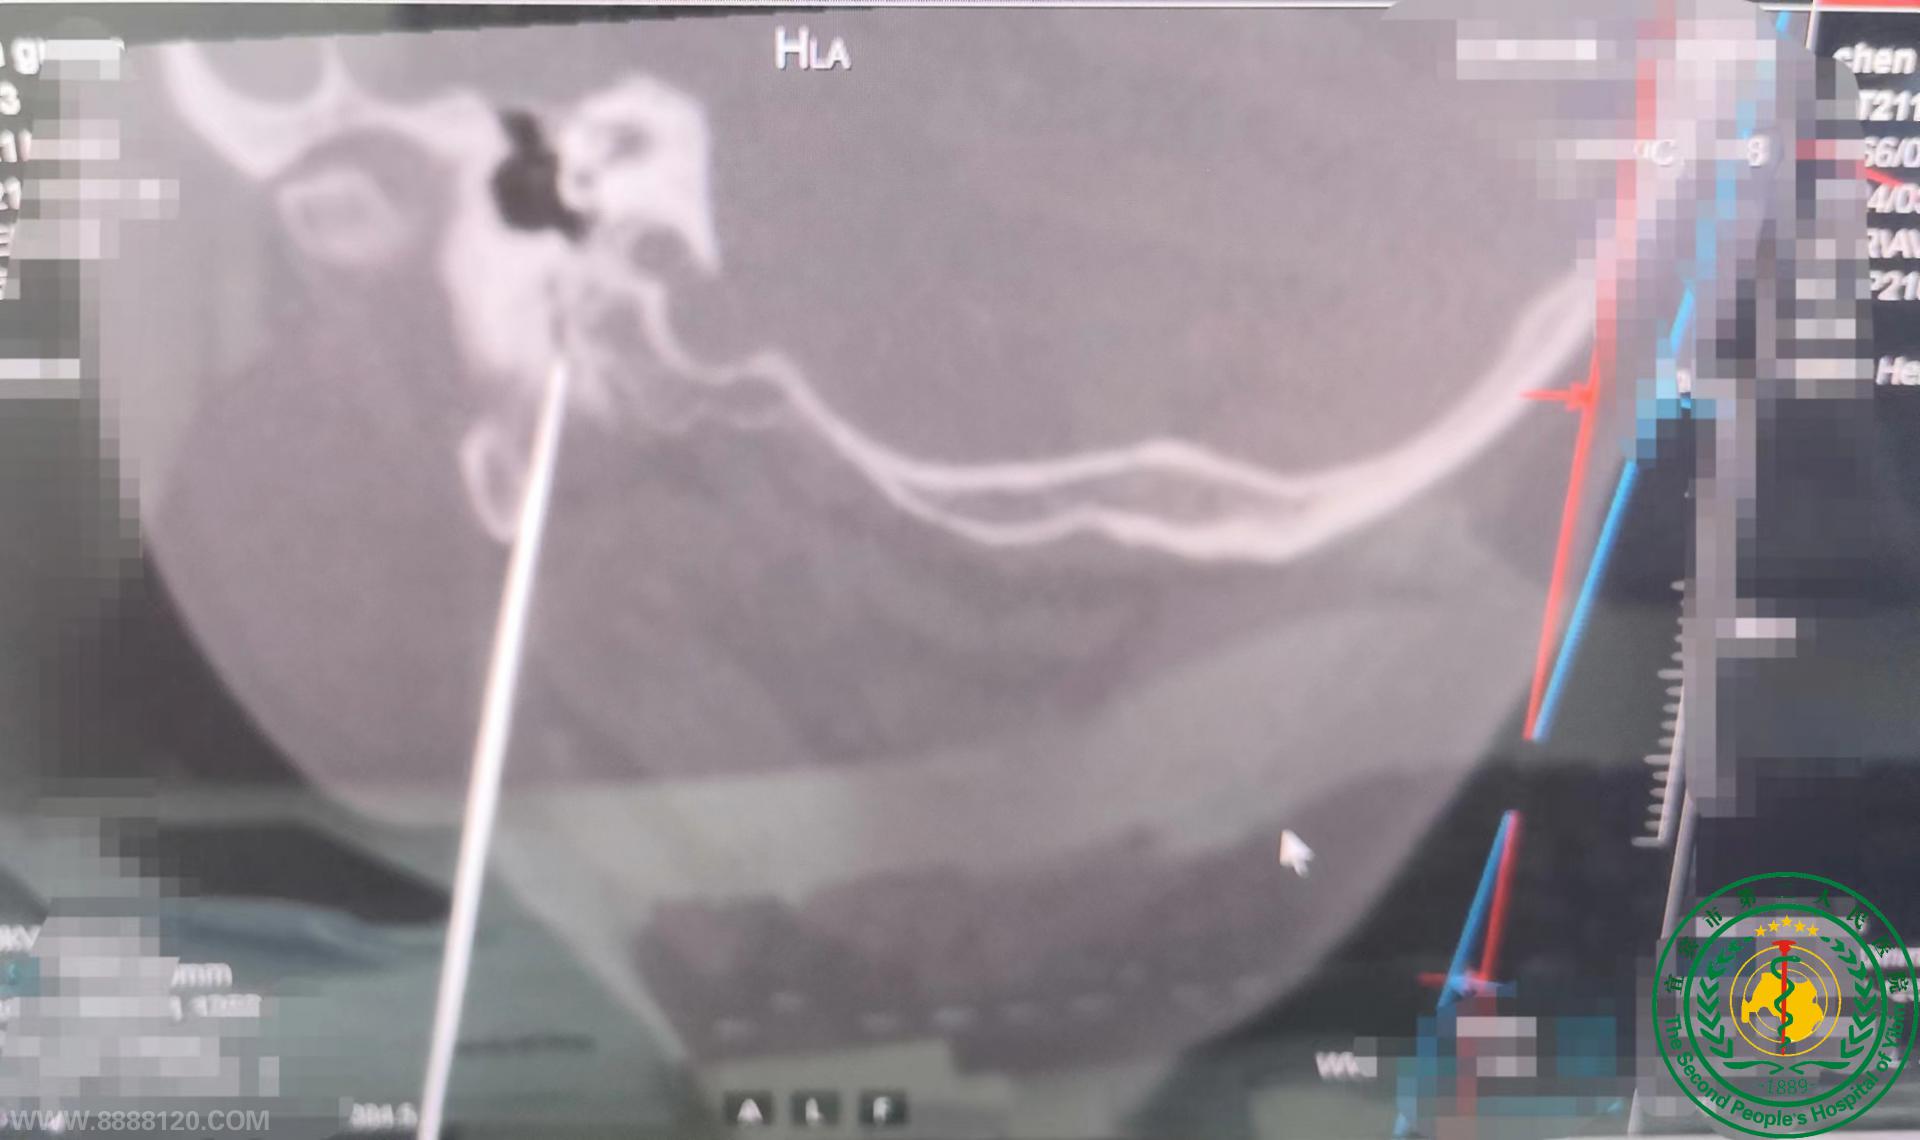

宜宾二医院率先在宜宾成功开展CT引导下经皮穿刺面神经射频脉冲手术

近日,宜宾二医院率先在宜宾成功开展CT引导下经皮穿刺面神经射频脉冲手术。患者为53岁男性患者,因右侧面部反复不自主抽搐1年来我院门诊,诊断为面肌痉挛,手术治疗为最佳治疗方法,经与患者及其家属充分沟通,告知患者及家属相关风险,患者及家属愿意选择在我院行CT引导下经皮穿刺面神经射频脉冲手术,遂经积极准备后由我院疼痛科医师成功实施该手术,术后患者非常满意并快速康复顺利出院。

4、CT引导下经皮穿刺面神经射频脉冲手术:创伤小、恢复快、并发症少。